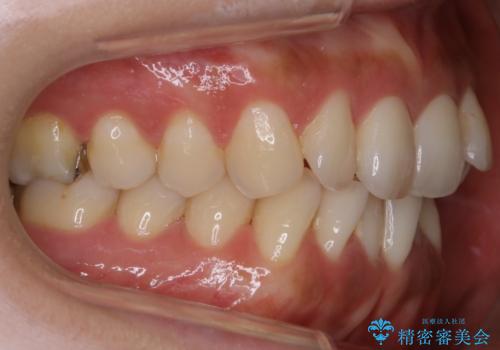

左側の噛み合わせは上の歯が前方に寄ってきてしまっていることが原因のズレがありました。

ガタつき自体は歯列の幅の拡大やディスキング(IPR)でほとんど解消可能でしたが、噛み合わせのズレは歯の移動が必要だったため、左上にマイクロインプラントを使用し噛み合わせの改善とガタつきの解消を同時に進めるという方針をとりました。

歯並びが悪くなる原因の一つに「歯列弓の狭窄」というものがあります。

奥歯や前歯が内側(舌側)に倒れ込んでしまったり、歯が生えてくる位置が内側になってしまうことにより歯並びのアーチが狭くなってしまうことを言います。

このような場合、歯並びのアーチを拡大してあげるだけでもガタつきを無くすためのスペースがかなり作れることがあります。